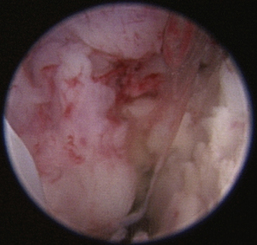

Nasopharyngeal Diseases

The hallmark symptom of nasopharyngeal disease is stertor. Discharge, sneezing, reverse sneezing, and hacking may be present variably. If the main complaint is noisy breathing and not productive sneezing with nasal discharge, the nasopharynx may be the site of primary disease. The most common primary problems in the nasopharynx in cats are inflammatory polyps and tumors.12,13 Cats with polyps are generally young and have a history of noisy breathing. Sneezing and mucopurulent nasal discharge may be present, but the chief complaint is stertor and increased respiratory effort. This is a problem that often requires otoscopic as well as rhinoscopic intervention. With the patient placed in dorsal recumbency, the soft palate is reflected rostrally with the use of a spay hook, and the polyp is removed via traction and avulsion (Figures 19-18 and 19-19). The eustachian tube orifices can generally be directly visualized and any remaining tissue removed, if present. Both ears should be carefully examined, and transtympanic bulla curettage should be performed to remove any middle ear proliferative tissue (see Chapter 20). In older cats with similar symptoms, a neoplasm in the nasopharynx is more likely, and rhinoscopy is often much more rewarding (Figure 19-20). Foreign bodies can become lodged in this area after vomiting or pharyngeal nasopharyngeal spasms induced by attempted swallowing of the foreign object. Nasal and nasopharyngeal stenosis after trauma, nasogastric reflux,14 and chronic rhinitis can occur in dogs and cats (Figures 19-21 through 19-23). Reflux can occur during general anesthesia and can be a helpful clue if postoperative symptoms arise and persist. Congenital choanal atresia and nasopharyngeal dysgenesis have also been reported in dogs.15,16 Nonspecific chronic inflammation of the nasopharynx causes a cobblestone appearance of the mucosa due to the formation of hyperplastic lymphoid follicles (Figures 19-24 and 19-25). Chronic inflammation may be the result of a lymphoplasmacytic rhinitis complex or sometimes may be secondary to otitis media and middle ear drainage of infected secretions via the eustachian tube. Otoscopy is recommended in any patient with nasopharyngitis of unknown origin. CT studies performed in a population of 45 cats with chronic sinonasal discharge revealed effusive bulla disease in 28% of symptomatic cats.17 Unfortunately, we are unable to differentiate primary and secondary pathology based on the concurrence of nasal and middle ear disease. Regardless of the knowledge of the primary cause, both inflammatory foci should be treated to achieve symptom relief.

Figure 19-20 Feline nasopharyngeal adenocarcinoma.

image